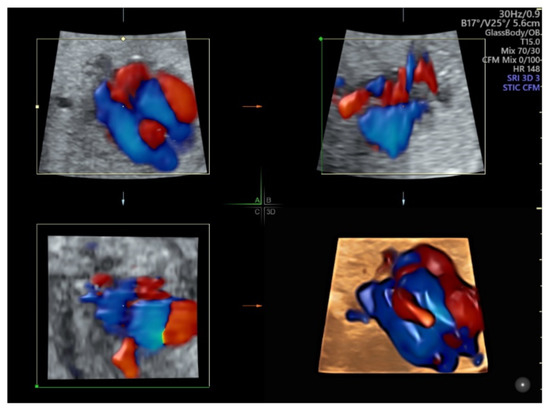

- Cardiac outflow tract abnormalities: use color flow, after a STIC volume acquisition, perform multiplanar/multi-slice analysis in a cine-loop of cardiac cycle.

5.2. Spatiotemporal Image Correlation